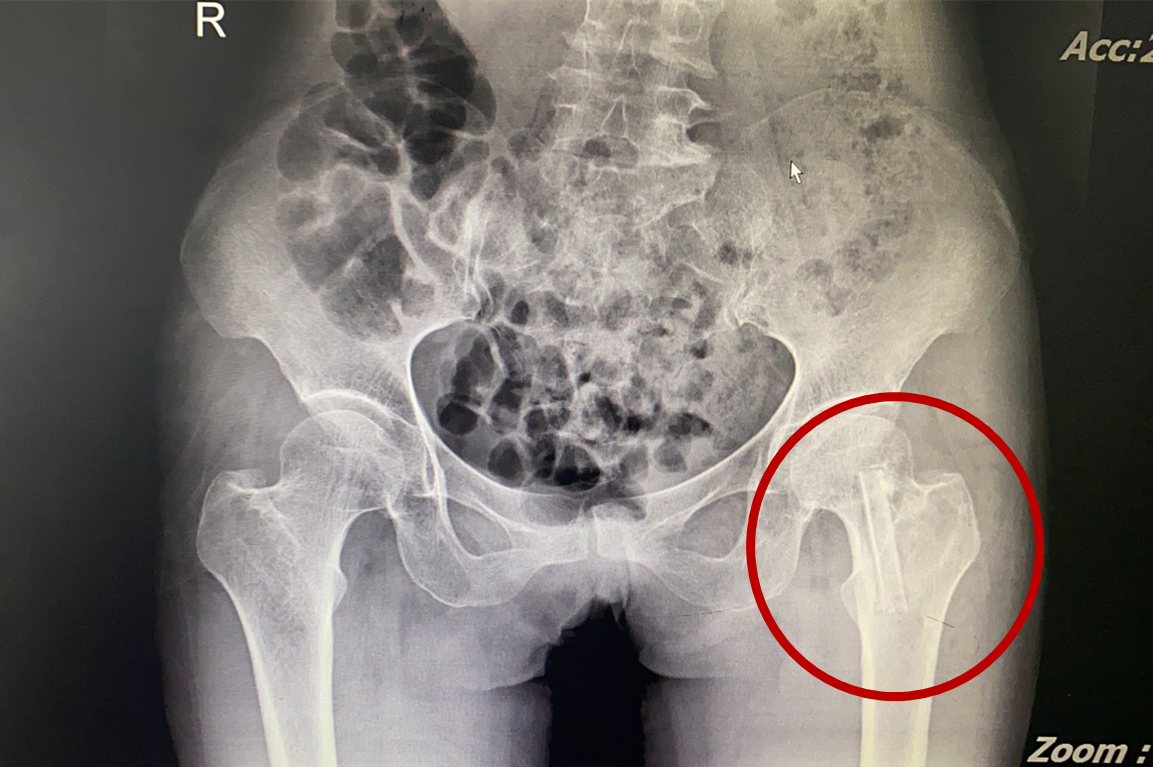

術(shù)后影像

“不死癌癥”股骨頭壞死患者治療新希望